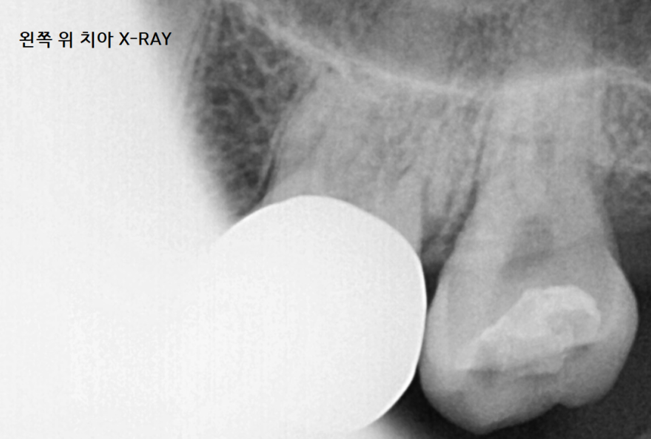

230731

처음부터 다시 검사를 시작

이번에는 특정 치아에서 딱! 통증을 호소하셨습니다.

통증을 없애는 것이 목표

신경치료가 되어있지 않은 치아라

신경치료 하고 통증이 감소하는지 지켜보기로 하였습니다.

미사역 치과에서 신경치료를 시작하였습니다.

일반적으로는 1-2번 치료로는 통증이 감소되지만

계속된 치료에도 아픔이 계속 되었습니다.

최후의수단 CT를 이용 검사해보았습니다.

230807

실선이 딱 보입니다.

치아 뿌리에 금이 가서

계속된 치료에도 통증 감소가 안됐었네요.

부러진 것이 아닌 이상

금이 간 경우 ,

뿌리 쪼개짐은 x-ray에서 보이지가 않습니다.